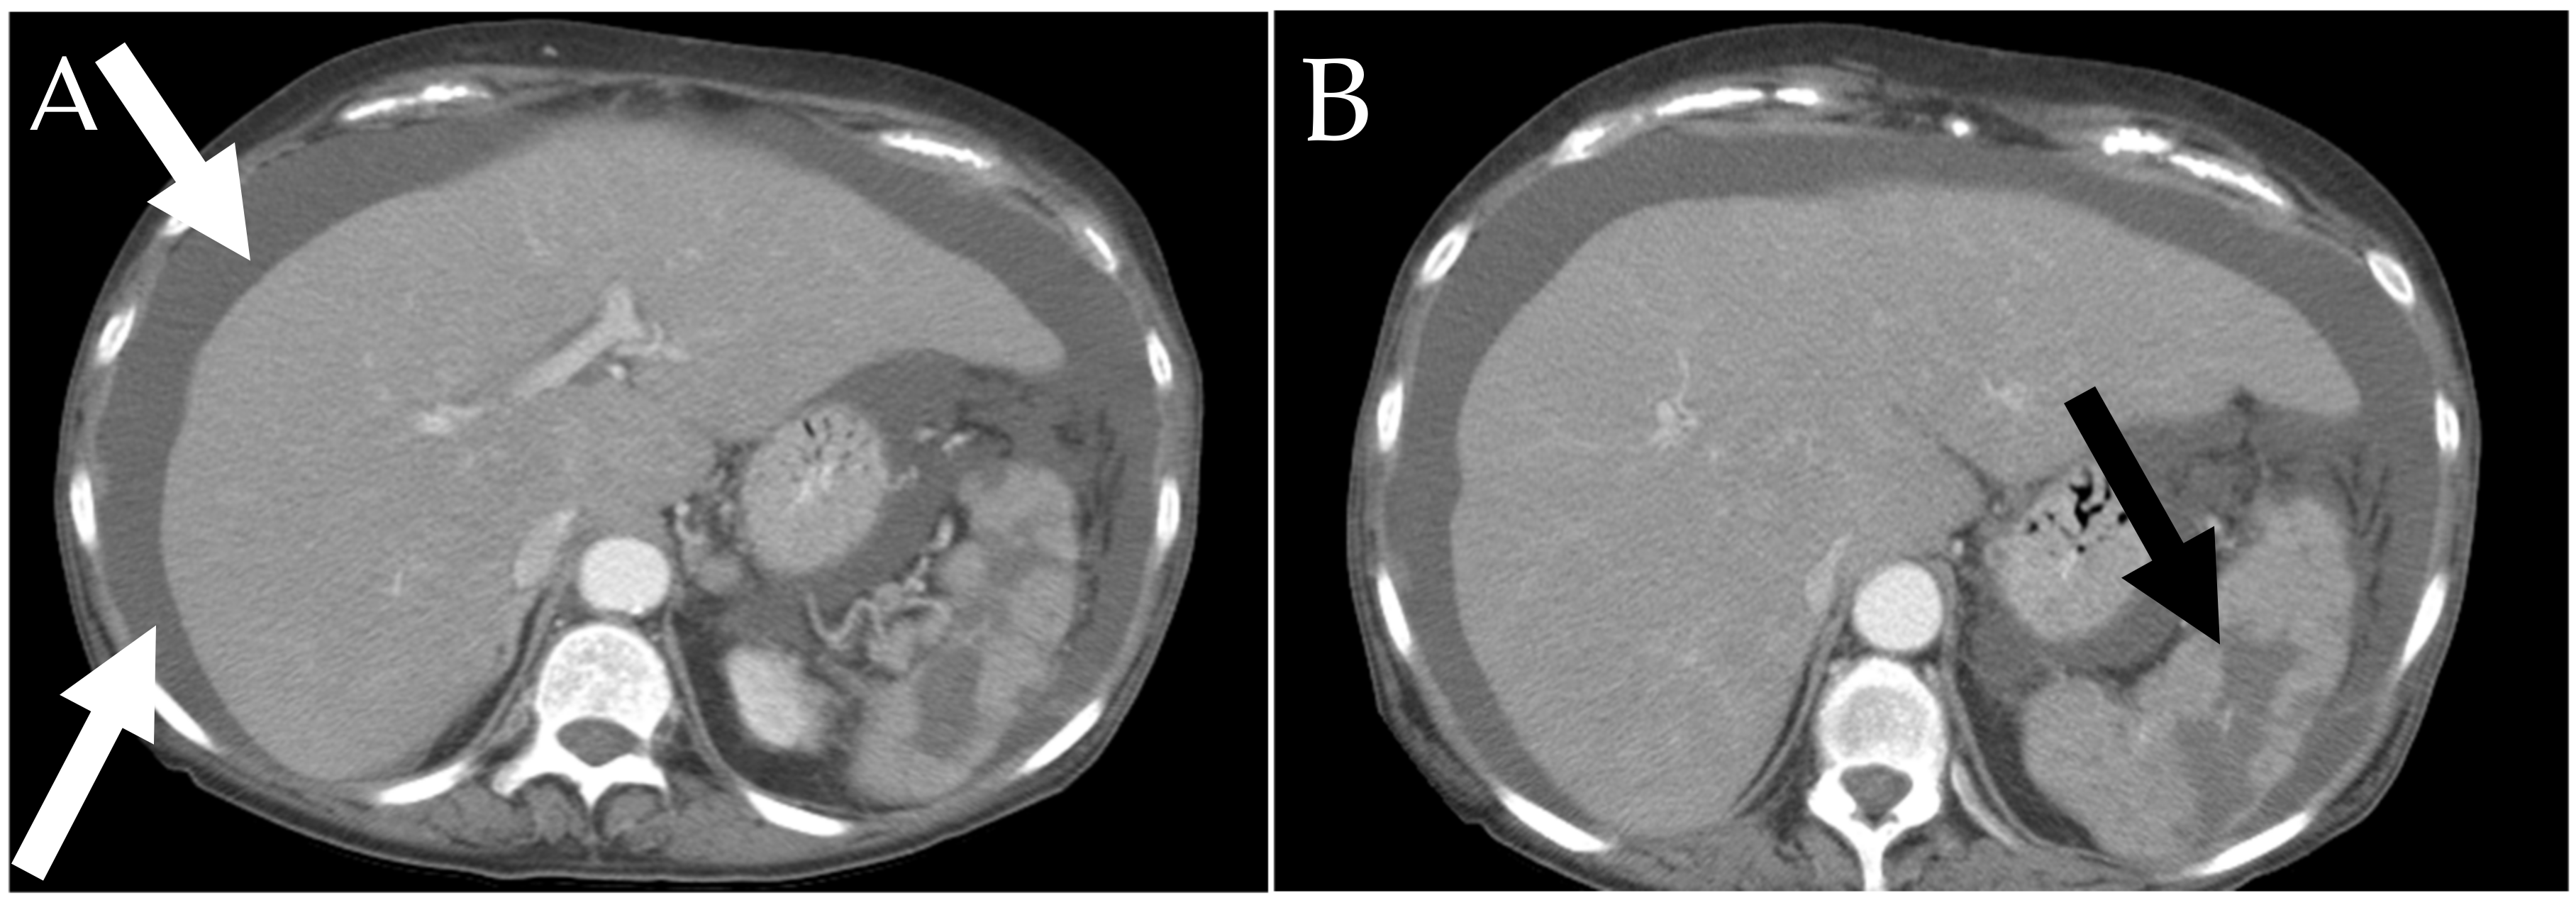

6.2. GI Tract, Liver and Spleen

6.2.2. Liver and Spleen

- Avila, N.A.; Ling, A.; Worobec, A.S.; Mican, J.A.M.; Metcalfe, D.D. Systemic mastocytosis: CT and US features of abdominal manifestations. Radiology 1997, 202, 367–372. [Google Scholar] [CrossRef] [PubMed]

- Narayanan, M.N.; Liu Yin, J.A.; Azzawi, S.; Warnes, T.W.; Turck, W.P.G. Portal hypertension and ascites in systemic mastocytosis. Postgrad. Med. J. 1989, 65, 394–396. [Google Scholar] [CrossRef] [PubMed] [Green Version]